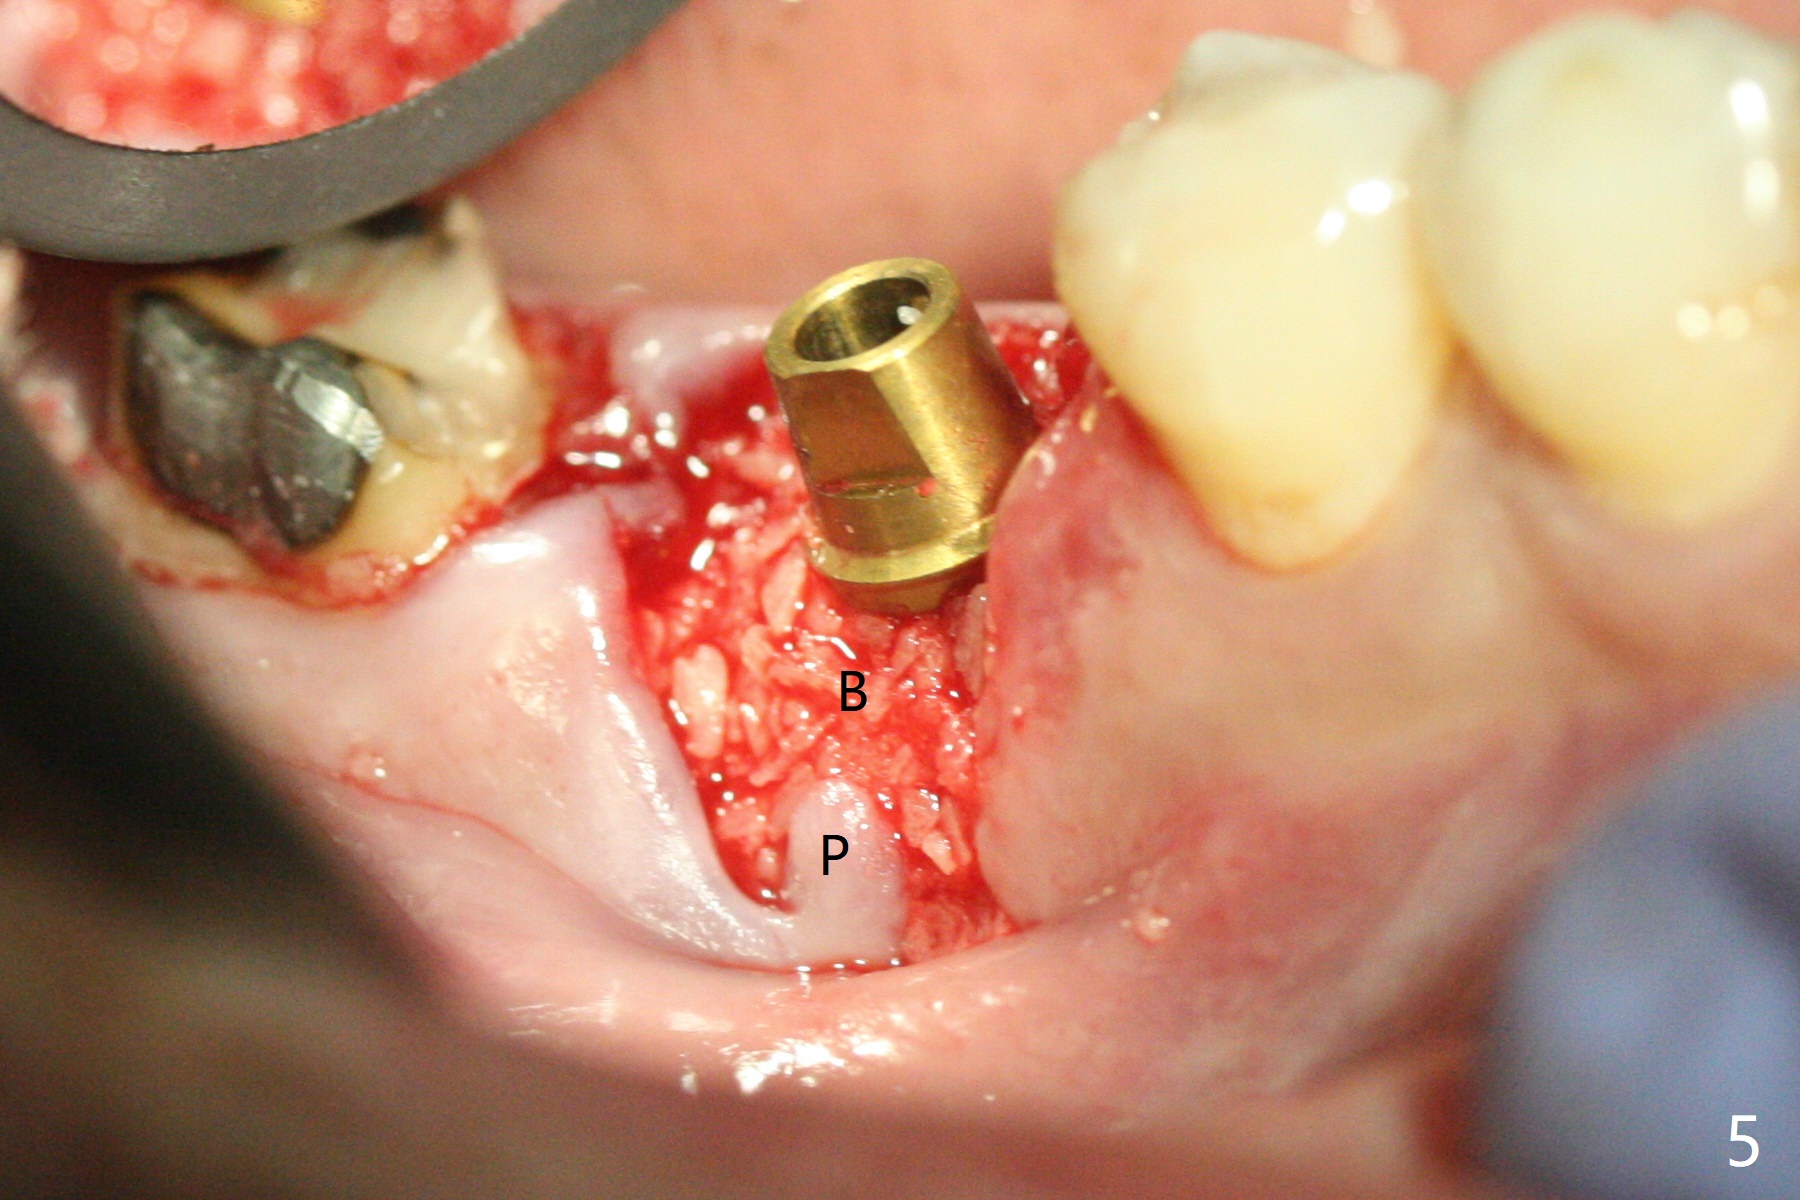

When the tooth #30 is extracted, the gingiva buccal to the septum (S in Fig.1,2 (P: papilla between the mesial and distal roots)) collapses. The latter is fixed with placement of a 4.5x11.5 mm implant (with guide), a 5.2x4(5) mm cemented abutment (Fig.3) and mixture of cortical bone (125μm – 850μm) and cortical/cancellous bone (.5-1 mm) with PRF (sticky bone, B in Fig.4-6). After placement of 2 pieces of PRF membrane over the bone graft, a temporary crown is fabricated to cover the buccal defect (Fig.7 T). Approximately 7.5 mm of the buccal threads are covered by the thick layer of bone graft (Fig.8 B). It is amazing to expect that the bone graft will turn into the buccal plate. It would be better if a narrower implant (4 instead of 4.5 mm) were placed more lingually or there were < 4 mm implant thread exposure (Fig.9). The gingiva reacts to the provisional nicely 7 days postop (Fig.10). The provisional will be removed for modification in 1 month. The patient complains of bad smell from the provisional 2 weeks postop. The provisional is removed. The distal socket (Fig.11 D) is healing, whereas the buccal bone graft (Fig.12 B) seems not have been vascularized. Pedicled flaps (I) should be transferred to cover the buccal bone graft. The margin of the provisional is polished, becomes short, and covered by periodontal dressing, which dislodges 2 days later. One week later, granulation tissue is forming apically with use of oral antibiotic and water jet (Fig.13 *). The bad smell reduces. The superficial loose bone graft changes colar and becomes detached 1 month 10 days postop. The temporary crown with the shortened buccal shelf is reseated for self cleansing or reapplication of PRF if needed (Fig.14).